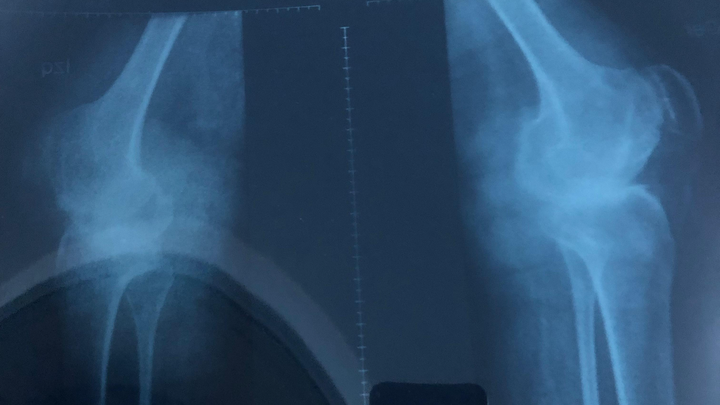

Soy Venezolana y nací con artritis Reumatoidea Juvenil, actualmente tengo 33 años, mi enfermedad a evolucionado a artritis Reumatoidea gotosa y en muchas partes ya tengo artrosis.

Hoy necesito prótesis en ambas caderas y ambas rodillas, las cuales son de reemplazo total.

Me fui de Venezuela a Argentina porque me dijeron que acá podrían ayudarme y aunque pueden operarme, no me pueden dar las prótesis adecuadas para mí condición de salud y edad. Las que me recomiendan son las de mejor calidad, durabilidad y por ende las más costosas!!. (Bioimpianti italiana ip magnam o Artrotek maxx americana. Para reemplazo total de rodillas y caderas)